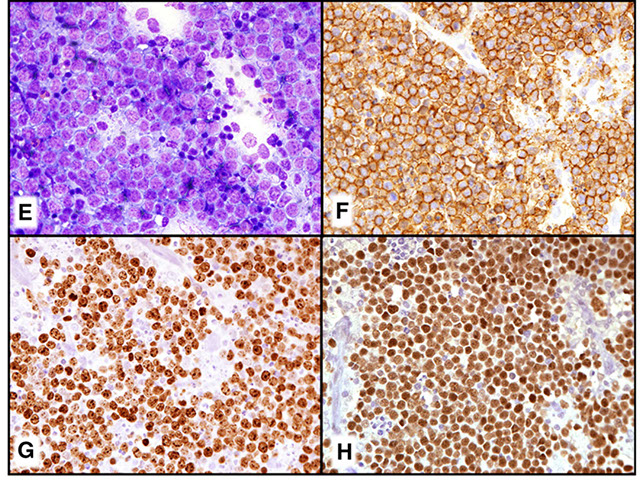

Burkitt lymphoma

Burkitt-like lymphoma with 11 q aberration

High-grade B-cell lymphoma

- High-grade B-cell lymphoma with MYC and BCL2 and/or BCL6 rearrangements

- High-grade B-cell lymphoma, NOS